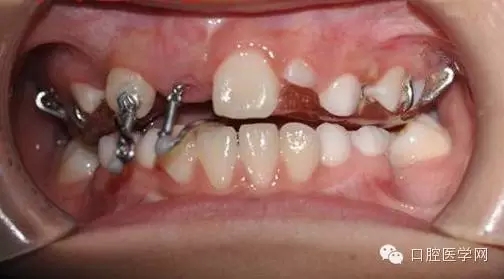

基本資料:男8歲、祖籍山東滕州、二年級(jí)。

主訴:門牙遲遲不長

現(xiàn)病史:右乳上一牙根滯留。

處理:拍片,CBCT,埋伏牙手術(shù)牽引。

埋伏牙在臨床較常見,可能于頜骨退化有關(guān),現(xiàn)以一例典型埋伏牙為例,講述簡(jiǎn)簡(jiǎn)單單牽引全過程,及注意事項(xiàng)。

小兒8歲發(fā)現(xiàn)右上門牙遲萌,右乳一殘根。